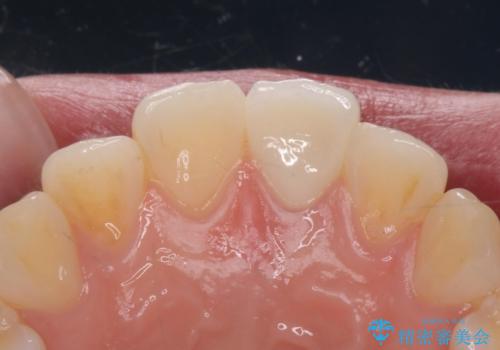

前歯の変色とガタつき ジルコニアクラウンでの修復

根管治療からやり直しを行った後、ジルコニアクラウンで修復することで、ガタつきと変色の両方を改善していきます。

ガタつきと変色の両方を改善することができ、大変喜んでいただけました。

少しのガタつきであれば、矯正治療を行わなくても改善できる場合があります。